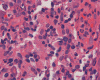

On low-magnification, the biopsy appears to be a piece of colonic mucosa without evidence of necrosis, erosion, or ulcer (Panel A). On medium-magnification, the lamina contains some vaguely formed collections of large cells (Ú in Panel B). On high-magnification, there are many large, round cells with eccentric nuclei. These are macrophages in clusters that are consistent with granulomas.  Many small, grayish to basophilic, vesicle-like structures are present in the cytoplasm (Panel in C). In other areas, these large, round cells do not really form small clusters and are admixed with lymphocytes (Panel D). Again, many small, grayish vesicle-like structures are present in these cells. A grayish to basophilic core is present and is surrounded by halo (Ú in Panel E).  These structures are most suggestive of microorganisms particularly fungus. On periodic acid Schiff (PAS), these vesicles appear bright purple-red (Panel F and G). The basophilic core is also strongly positive for PAS stain (Panel G). These microorganisms appear dark with Gomori methamine silver stain (Panel H and I).

Comment: The pathologic changes in this case are morphologically consistent with histoplasmosis. The patient is immunocomrpomised (HIV-2 positive). Typical to these cases are poorly formed granuloma as illustrated in this case.

In immunocomprised patients that have defective cellular immunity, granuloma formation may be rather indistinct as illustrated in our case. The yeast form of Histoplasma capsulatum is found in tissue and they are usually under 5 mm in diameter and appear as ovoid yeasts.  The lung is the most affected organ. Granuloma formation, typically multiple, with extensive caseous necrosis and a variable amount of calcifications are the typical pathologic changes in the lung. These granulomas are often demarcted from the surrounding tissue by a fibrous wall. Granulomas in the lung can get quite calcified with time. The pulmonary nodules can also enlarge slowly to give a wrongful clinical impression of neoplasm, the so-called histoplasmoma. The living yeast in tissue, often occur in clusters, has a basophilic center and a translucent halo that represents the capsule. They are often engulfed by histiocytes as illustrated in this case. Dead organisms appear eosinophilic and cannot be detected easily in granuloma by hematoxylinj-eosin stain. The microorganism is numerous and can be identified on routine hematoxylin-eosin stain with astute observation and high index of suspicion. Typically, there are numerous yeasts and they are present even in heavily calcified nodules or granulomas.